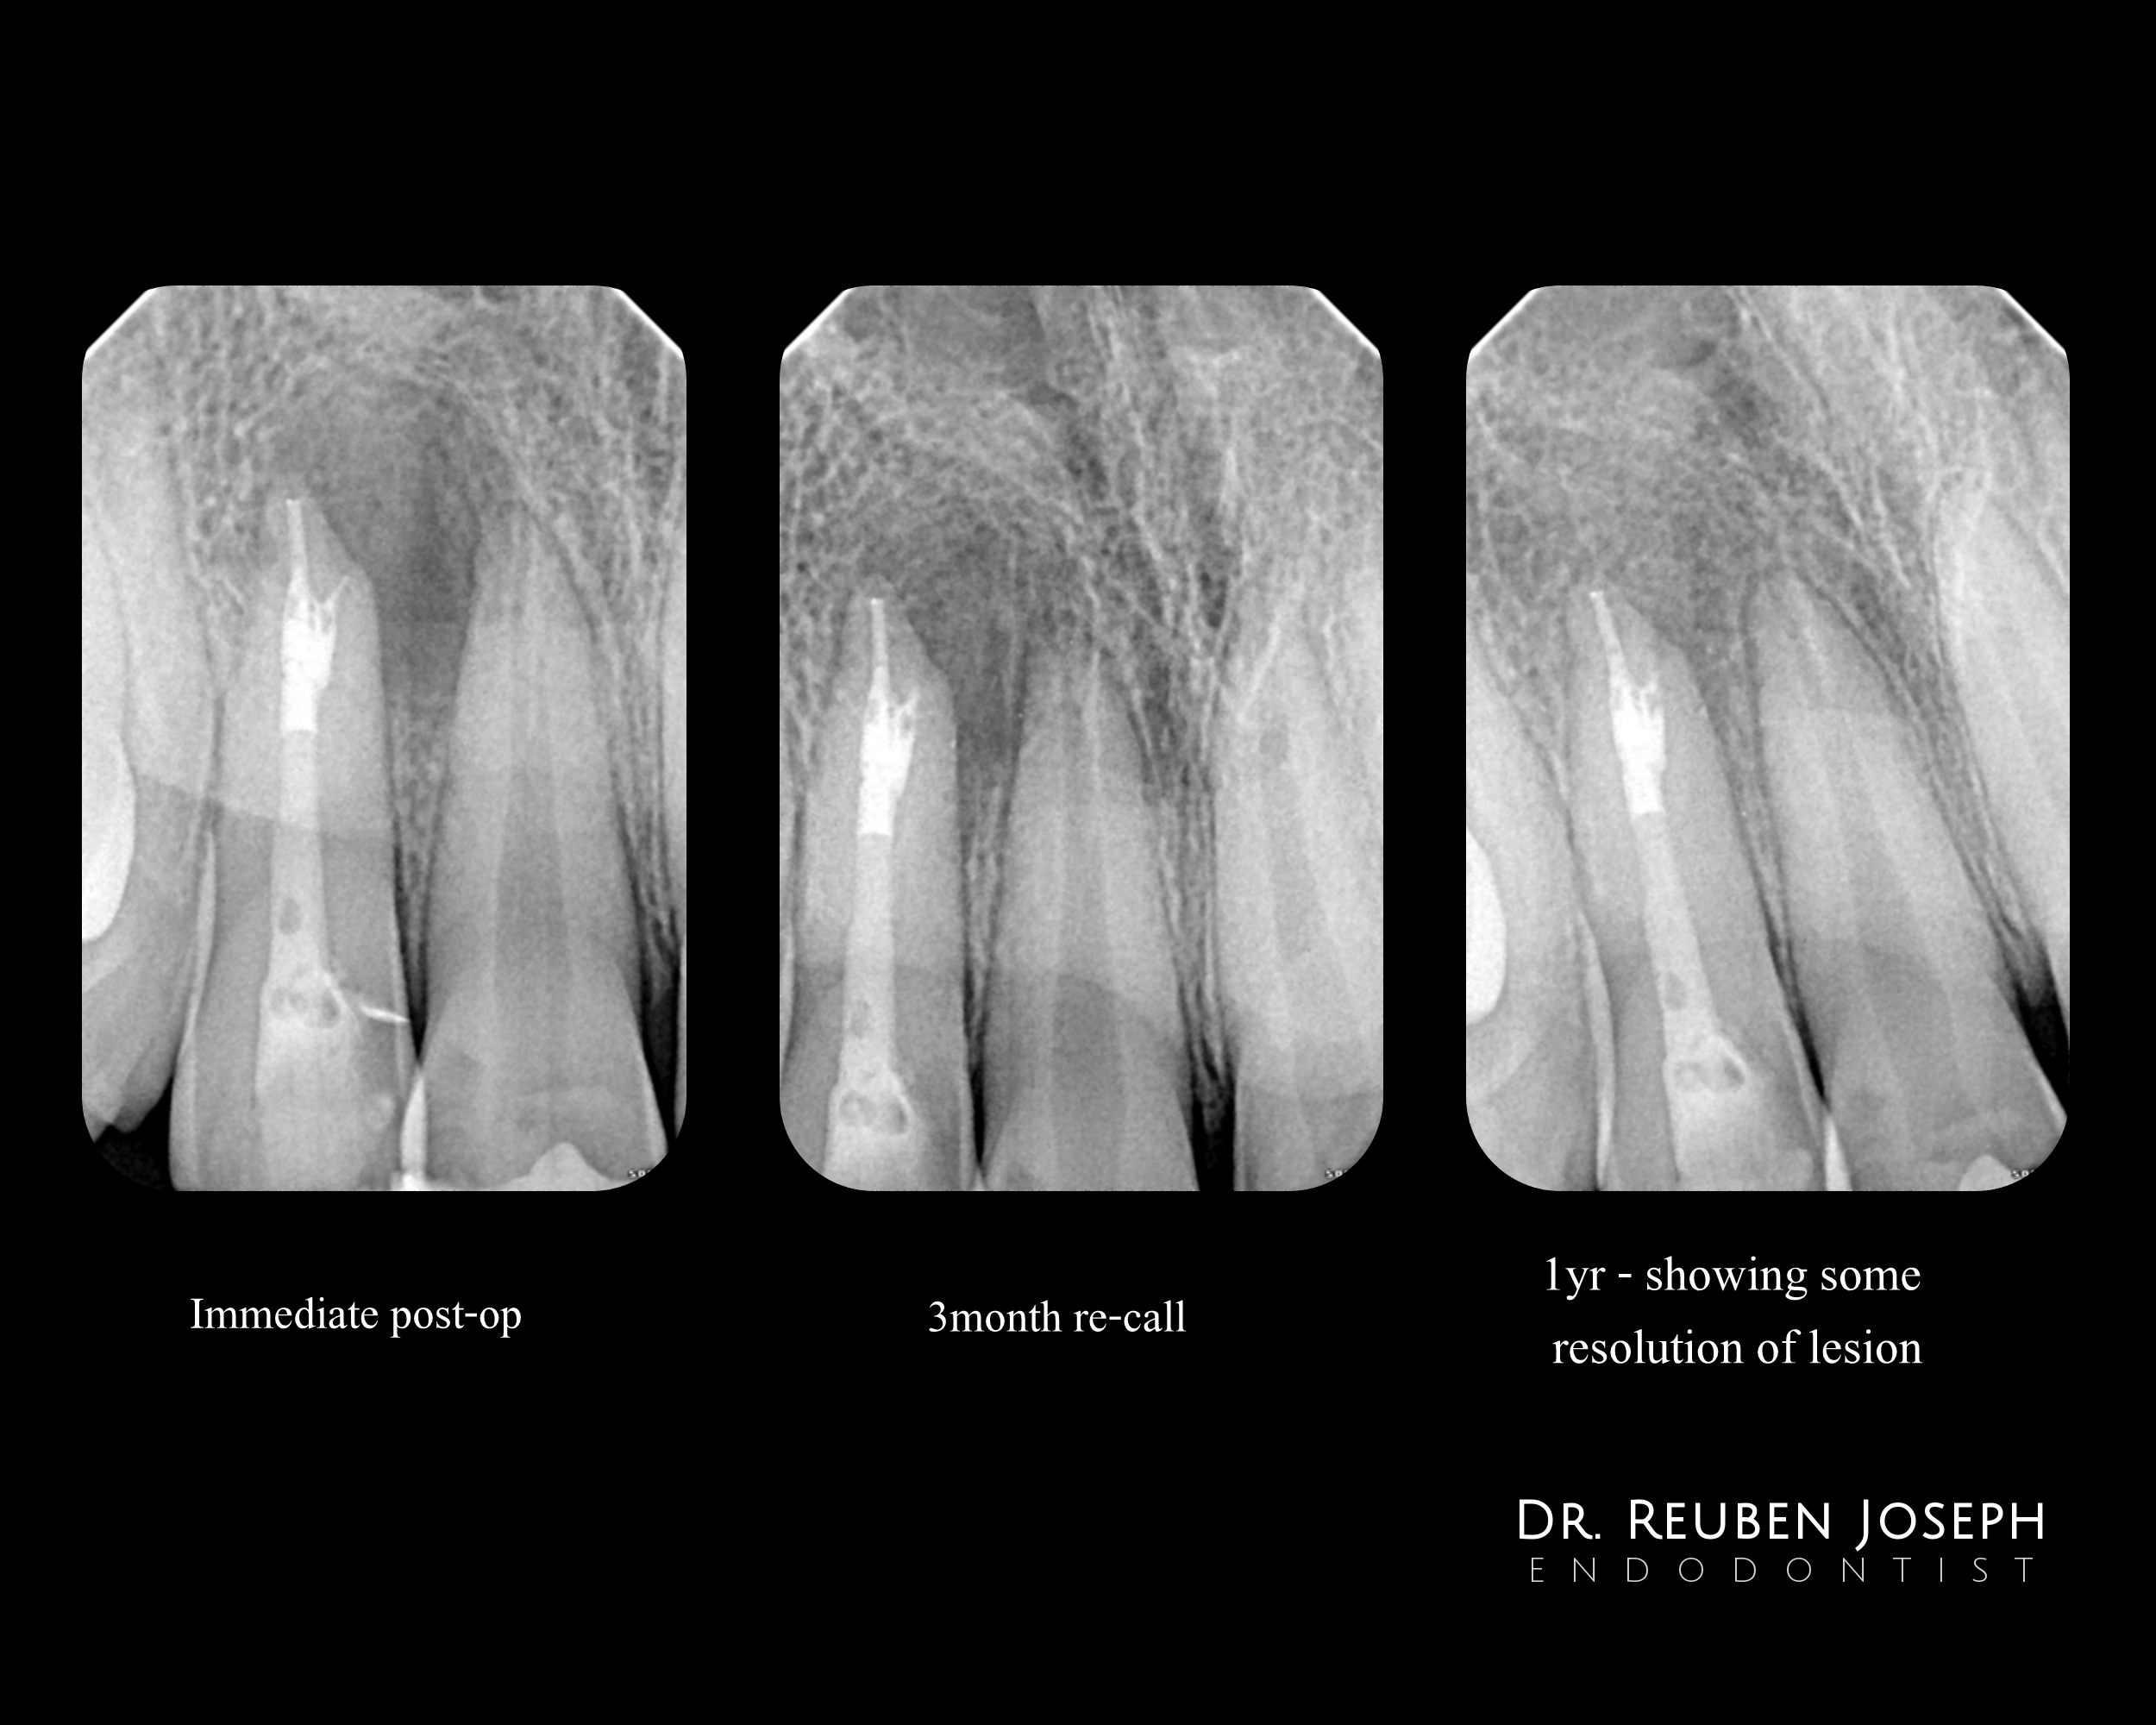

2nd visit – Decided to obturate using the rapid flow technique as the GP kept buckling due to the sharp apical curve and the extra lateral canal had to be filled as well. A blob of thermoplasticized GP placed in the main canal and condensed followed by the same in the lateral canal as well. The rest of the canal back-filled and posts cemented for some root re-inforcement

1yr review showed good progressive healing

And I agree, the radiographic finding suggests the area is resolving. Will be nice to see the CBCT in another year.